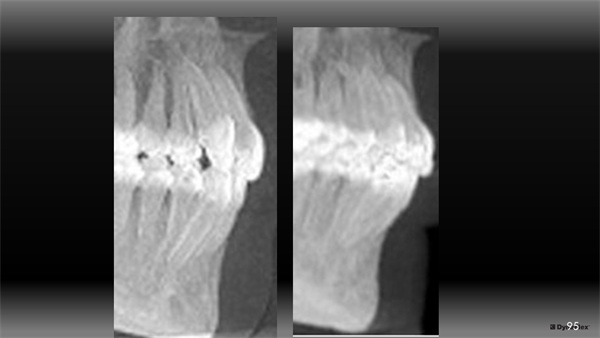

Next, we considered micro/tooth aesthetics and occlusion. If our treatment goal is to advance the A-P position of her upper incisors to benefit her lip position and her upper incisor aesthetic projection within her smile, this demands that the lower incisors will be proclined/rolled forward as well to properly couple with that new forward position of the uppers. When considering changes in lower incisor position, visualizing the mandibular alveolar housing can be valuable. Looking at CBCT images (Fig. 4), she had what I would grade as a thicker type of alveolar housing in the mandibular arch. The possibility of her periodontally tolerating that proclining/rolling forward of her lower incisors was reasonable to me.1

The Architects of the Lips: Part 4

Fig. 4

Figure 12 shows that the lower incisors also rolled forward within her thick alveolar housing to couple with this more forward position of her maxillary incisors (pre-tx on the inside, post-tx on the outside). If she had a thinner type of housing, it might have impacted my tolerance for this movement.

Fig. 12

There are obviously many ways to treat this case and I don’t present my way as the best or only way to treat Rylee. Her orthodontic treatment could have been done well without advancing her upper incisors or even by way of extracting permanent teeth. Treatment goals set the course and those vary greatly. For me, it started by looking outside-in and appreciating her lips and what was possible to enhance their presentation, noticing a deficiency in the aesthetic A-P projection of her upper incisors in her smile, and then visualizing her mandibular housing via CBCT to assess how this occlusal change might be tolerated.